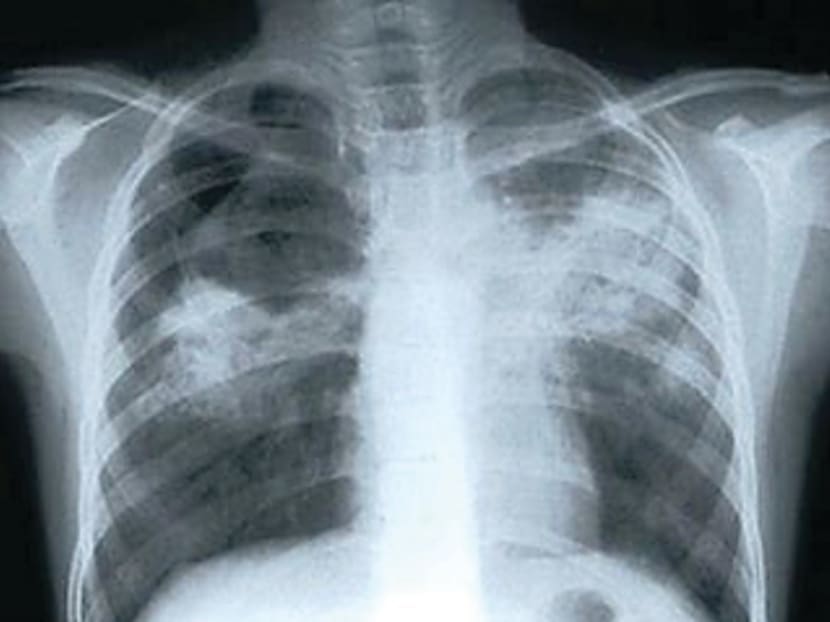

An x-ray showing lungs affected by tuberculosis. TODAY file photo

A bacterial infection that attacks the lungs and can cause coughing, fever, night sweats and weight loss, TB is one of the top 10 causes of death worldwide today.